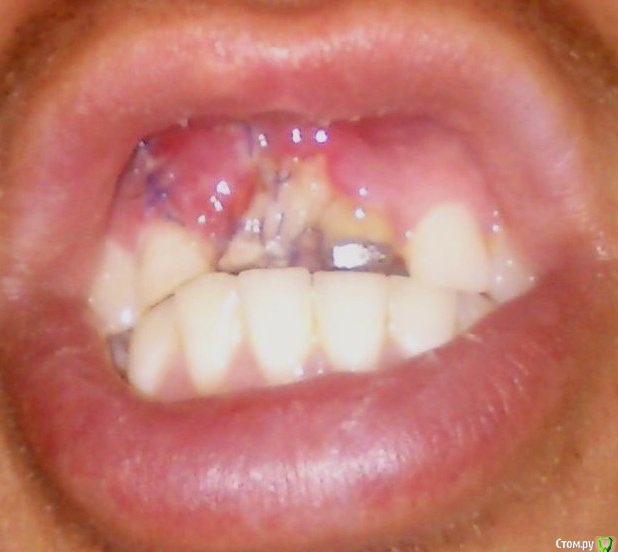

Здравствуйте, необходим свежий взгляд на мою проблему. С раннего детства в возрасте 7-8 лет получил травму, сломав два  верхних передних зуба (11, 21). У них были удалены нервы и запломбированы каналы, в возрасте 17-18 лет надеты постоянные, спаянные коронки. В возрасте 25 лет из-за полученной травмы (неудачного падения) был сломан корень 21 зуба, что привело к его удалению. На второй зуб (11) была установлена культевая вкладка и одета коронка. Через год после удаления решился на имплантацию утраченного зуба. Лечащий врач посоветовал нарастить кость для более правильной и надежной  установки импланта и возможности  дальнейшего протезирования с эстетической точки. Провели костную пластику, установлена была мембрана коллагеновая и подсыпан костный материал (не свой) под нее. То ли у меня отторжение этого материала произошло, то ли из-за недостаточного объема десны инфицировалась мембрана, так как оперирующий меня врач с трудом наложил операционные швы, ему пришлось натягивать десну за счет соответствующих надрезов ее у соседних зубов. Операция длилась около двух часов. Оказывается, у меня срослась десна с костью, или проросла в кость, из-за свича давнишнего, точно не знаю. После операции (3-4 дня) десна в области подсадки костного материала поменяла цвет и начала истончаться и провисать. Десна не заживала, и в месте подсадки костного материала просто рассосалась. Лечащий врач сказал мне, что все заживет со временем и посоветовал наносить пасту Солкосерил дентальный на поверхность дефекта.

Подскажите, пожалуйста, восстановится ли данный участок десны самостоятельно или необходимо хирургическое вмешательство?

Для дальнейшей имплантации необходима повторная костная пластика?

post-41404-0-41396800-1418589331_thumb.jpg

Самостоятелно дефект не восстановится, понадобится повторная костная пластика и пластика мягких тканей, скорее всего не одна